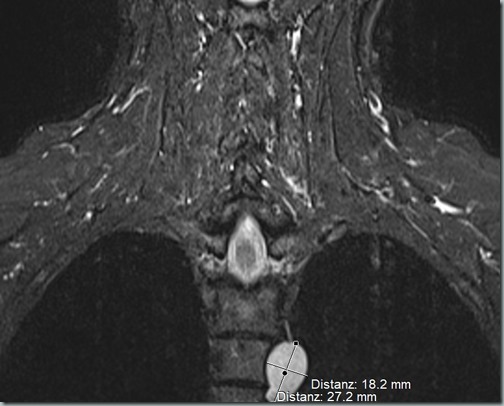

Positiver Nebeneffekt des MRTs: ich hab die Zyste mal wieder auf Bildern. Immer noch knappe 1,8×2,7 cm, also kein Wachstum.